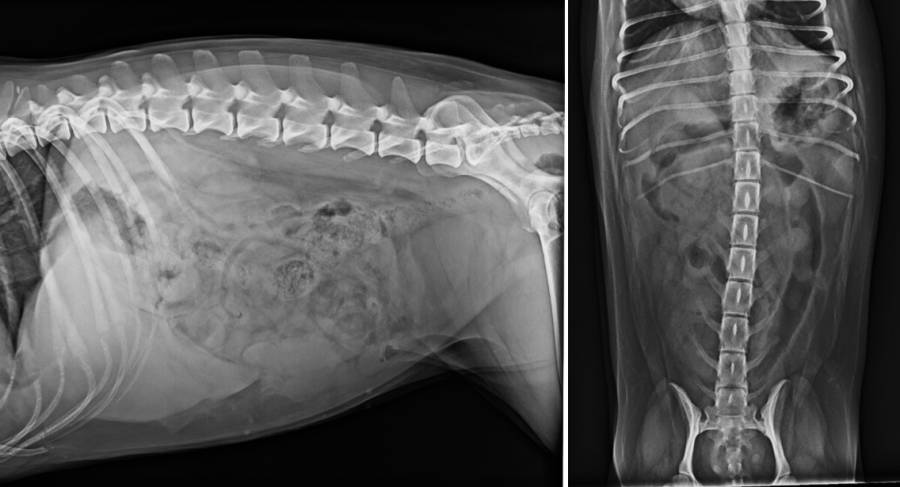

Röntgen Abdomen

Röntgen Wirbelsäule